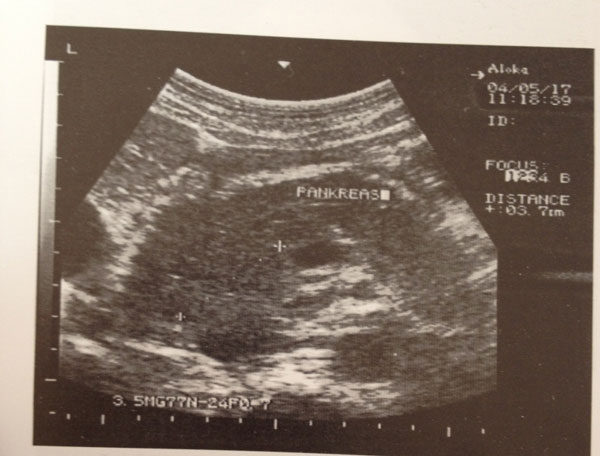

Te dhenat e ekzaminimit ekografik.

- Pankreasi eshte i zmadhuar dhe hipoekogjen ne krahasim me heparin. Ne stadet fillestare mund te jete me ekogjenecitet normal.

- Pankreasi eshte me konture te crregullta dhe jo te qarta.

- Si pasoje e rritjes se dimensioneve te pankreasit ai komprimon e sposton poshte venen splenike.

- Duktusi pankreatik zgjerohet mbi 2.5 mm

- Prania e likidit ne Lesser Sac dhe sinusin freniko-kostal te majte.

- Zmadhimi i kokes se pankreasit mund te komprimoje koledokun dhe te japi obstruksion te shkalleve te ndryshme.

Fig 1: Ekzaminim ekografik ku paraqitet pankreasi i zmadhuar, hypoekogjen, me konture jo te qarta.